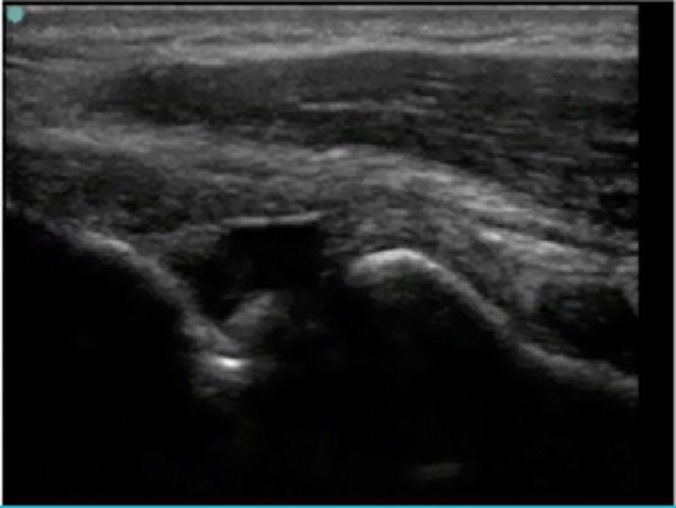

Elbow Intra-articular Injection Radiocapitellar Joint Image